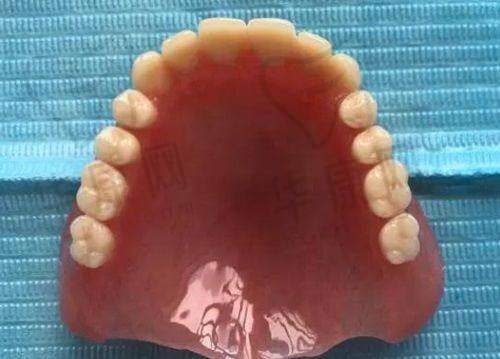

术后,刘鹏医生详细地跟我说了注意事项,还叮嘱我按时吃药、定期复诊。刚开始的几天,伤口有点轻微的肿痛,但都在我能忍受的范围内。按照刘医生的嘱咐,我注意饮食,保持口腔清洁。大概过了一周左右,肿痛就基本消失了。而且让我惊喜的是,我特别快就能正常吃饭了,种植牙的稳定性真的特别不错。

现在,我的种植牙已经用了一段时间了,成效真的超出了我的预期。外观上和真牙几乎没有区别,吃东西的时候也特别给力,啃排骨都没问题。我真的特别感谢北海柏乐口腔的刘鹏医生和他的团队,是他们不错的技术和贴心的服务让我重新拥有了健康的牙齿。如果你也有牙齿缺失的困扰,不妨来北海柏乐口腔找刘鹏医生试试即刻种植牙。